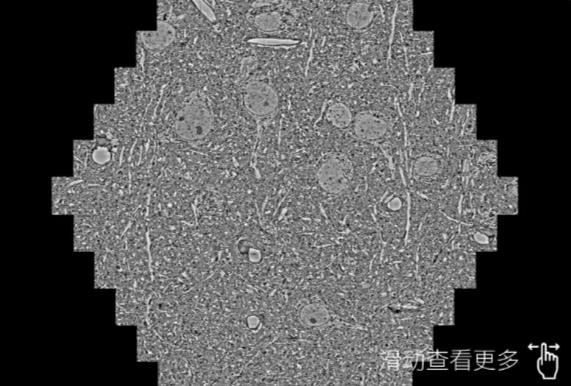

鼠脑切片。左图使用池州蔡司池州扫描电镜MultiSEM706对165μmx143pm面积区域成像,耗时仅需1.5秒。右图为鼠脑切片中30μm区域放大效果。样品由芝加哥大学B.Kasthuri提供。

使用蔡司高速池州扫描电镜MultiSEM对1mm²人脑皮层组织进行高分辨成像,并对其中的各种细胞结构进行三维重构分析。左图展示了2x3mm²组织平面中锥体神经元的三维重构效果。右图显示了局部体积神经元三维重构。图像由哈佛大学chtman实验室提供,渲染图由D. Berger 制作。